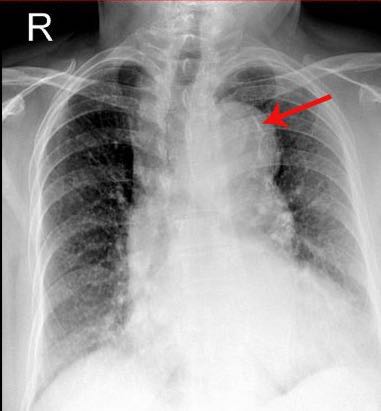

近期北京天坛医院心内科成功救治了一位主动脉夹层的患者,将患者从死亡线上挽救回来。故事要从老王半夜胸痛说起。老王,今年51岁,夜里十点钟洗澡后突发持续性胸背痛,大汗淋漓,坐立不安,家属立即把他送到北京天坛医院急诊。天坛医院心内科和急诊科联合成立的胸痛中心立即启动胸痛救治的绿色通道,由于老王心电图表现不是典型的心肌梗死图形,但又无法排出心肌梗死,心内科老王急诊行冠状动脉造影检查,但却未发现异常,排除了急性心肌梗死。老王怎么了?导致他剧烈胸痛的元凶到底是谁?北京天坛医院心内科胸痛中心小组人员经仔细询问和检查,发现了一个可疑的迹象,老王胸片的心影比一般人宽很多,于是及时为老王安排了血管增强CT的检查,经检查确诊为主动脉夹层,并急诊转心血管外科急诊手术治疗。由于救治及时,老王现已转危为安。那么,什么是主动脉夹层呢?

1、胸片(CR):可看到主动脉球扩大、纵膈增宽,但不能作为确诊手段。